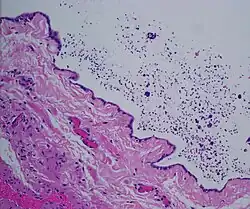

Spermatocele

Spermatocele is a fluid-filled cyst that develops in the epididymis.[3] The fluid is usually a clear or milky white color and may contain sperm.[4] Spermatoceles are typically filled with spermatozoa[5] and they can vary in size from several millimeters to many centimeters. Small spermatoceles are relatively common, occurring in an estimated 30 percent of males.[6] They are generally not painful. However, some people may experience discomfort such as a dull pain in the scrotum from larger spermatoceles.[7] They are not cancerous, nor do they cause an increased risk of testicular cancer. Additionally, unlike varicoceles, they do not reduce fertility.[7]